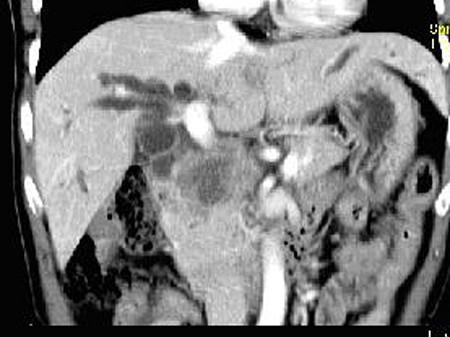

问题 患者,男,51岁,右上腹隐痛2月余,CT扫描如图,最可能的诊断是 ( )

选项 A.胆囊癌伴肝门胰头周围转移 B.胆囊息肉 C.胆囊黄色肉芽肿 D.慢性胰腺炎并胆囊息肉 E.胆囊腺瘤及慢性胰腺炎

答案 A